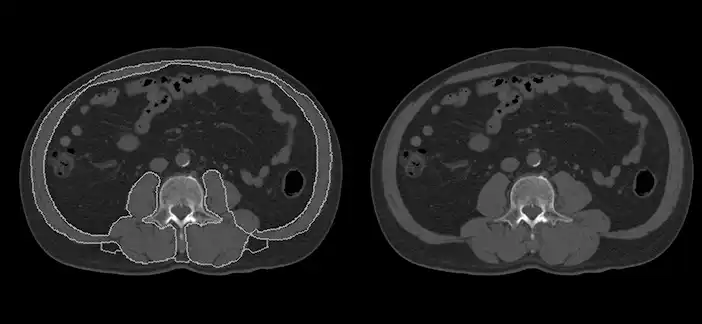

画像の経時変化を用いた研究

微細な経年変化を捉えて疾病を予測